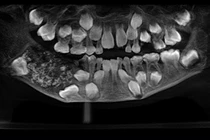

Thông thường, các biểu hiện của bệnh nha chu giống như bệnh sâu răng, bao gồm nướu bị đỏ và sưng. Tuy nhiên, nếu bạn thấy phần dưới cùng của răng có 3 màu sắc này tích tụ thì cũng hãy nghĩ đến khả năng là dấu hiệu cảnh báo viêm nha chu.

Chia sẻ trên trang Express Daily, bác sĩ Mani Bhardwaj, Giám đốc lâm sàng và nha sĩ chính tại Tập đoàn Nha khoa Smile Studios, cho biết: "Trong bệnh nha chu tiến triển, bạn có thể thấy nhận thấy ở xung quanh cổ răng gần đường nướu có tích tụ các cao răng màu xanh lá cây, nâu, vàng sẫm". "Kèm theo đó là các triệu chứng khác như hơi thở hôi, nướu có thể có dấu hiệu co hoặc tụt lại và răng có thể trở nên lỏng lẻo, bị nghiêng do mất nền xương", BS Mani nói thêm.